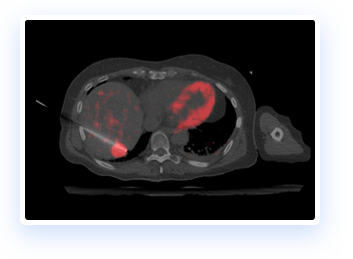

IGTFusion can visualize and register 3D image data from multiple modalities, including CT, PET, and MR images automatically.